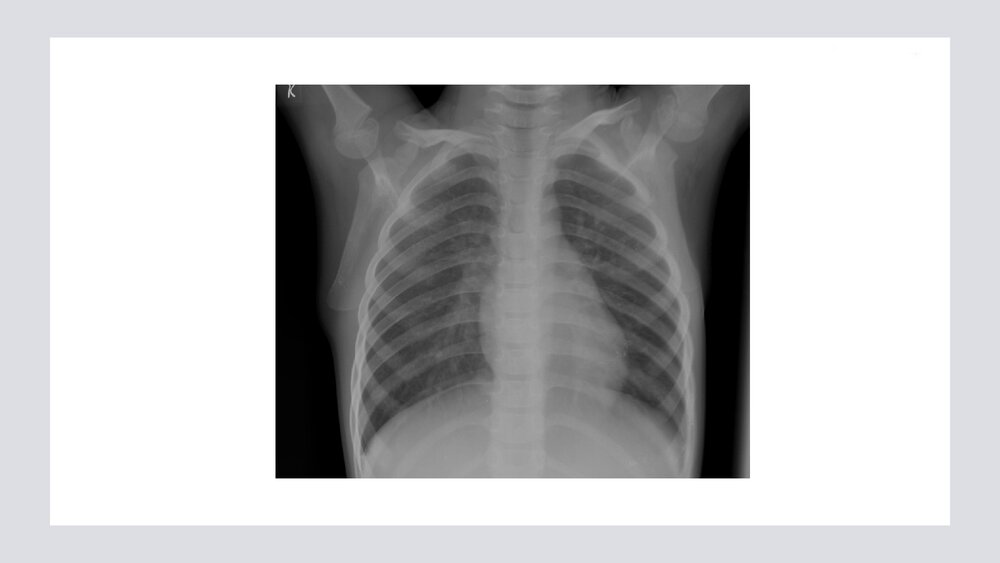

新生儿肺炎新生儿肺炎汇报人:xxx时间:xxx为我国新生儿最常见疾病之一,是新生儿死亡的主要原因。新生儿肺炎可发生在宫内、分娩过程中或出生后,由细菌、病毒、霉菌等引起。病因﹙宫内感染性肺炎﹚血行(胎盘)传播:病毒最常见,巨细胞病毒、单纯疱疹、肠道病毒、腺病毒;肺炎多为全身感染的一部分。吸入污染的羊水与窒息和污染羊水下行性吸入有关;病原为孕母阴道细菌(大肠埃希菌、克雷白菌、B组链球菌、金葡菌)和病毒病因(产时感染性肺炎)见于发热、患羊膜炎孕妇娩出的新生儿或急产、断脐消毒不严分娩过程中吸入阴道内污染的分泌物病原体:杆菌、B组链球菌、沙眼衣原体、解脲脲原体、TORCH病毒病因(出生后感染性肺炎)分为医院或社区感染两类,前者以细菌感染多见;后者以细菌和病毒多见。血行...